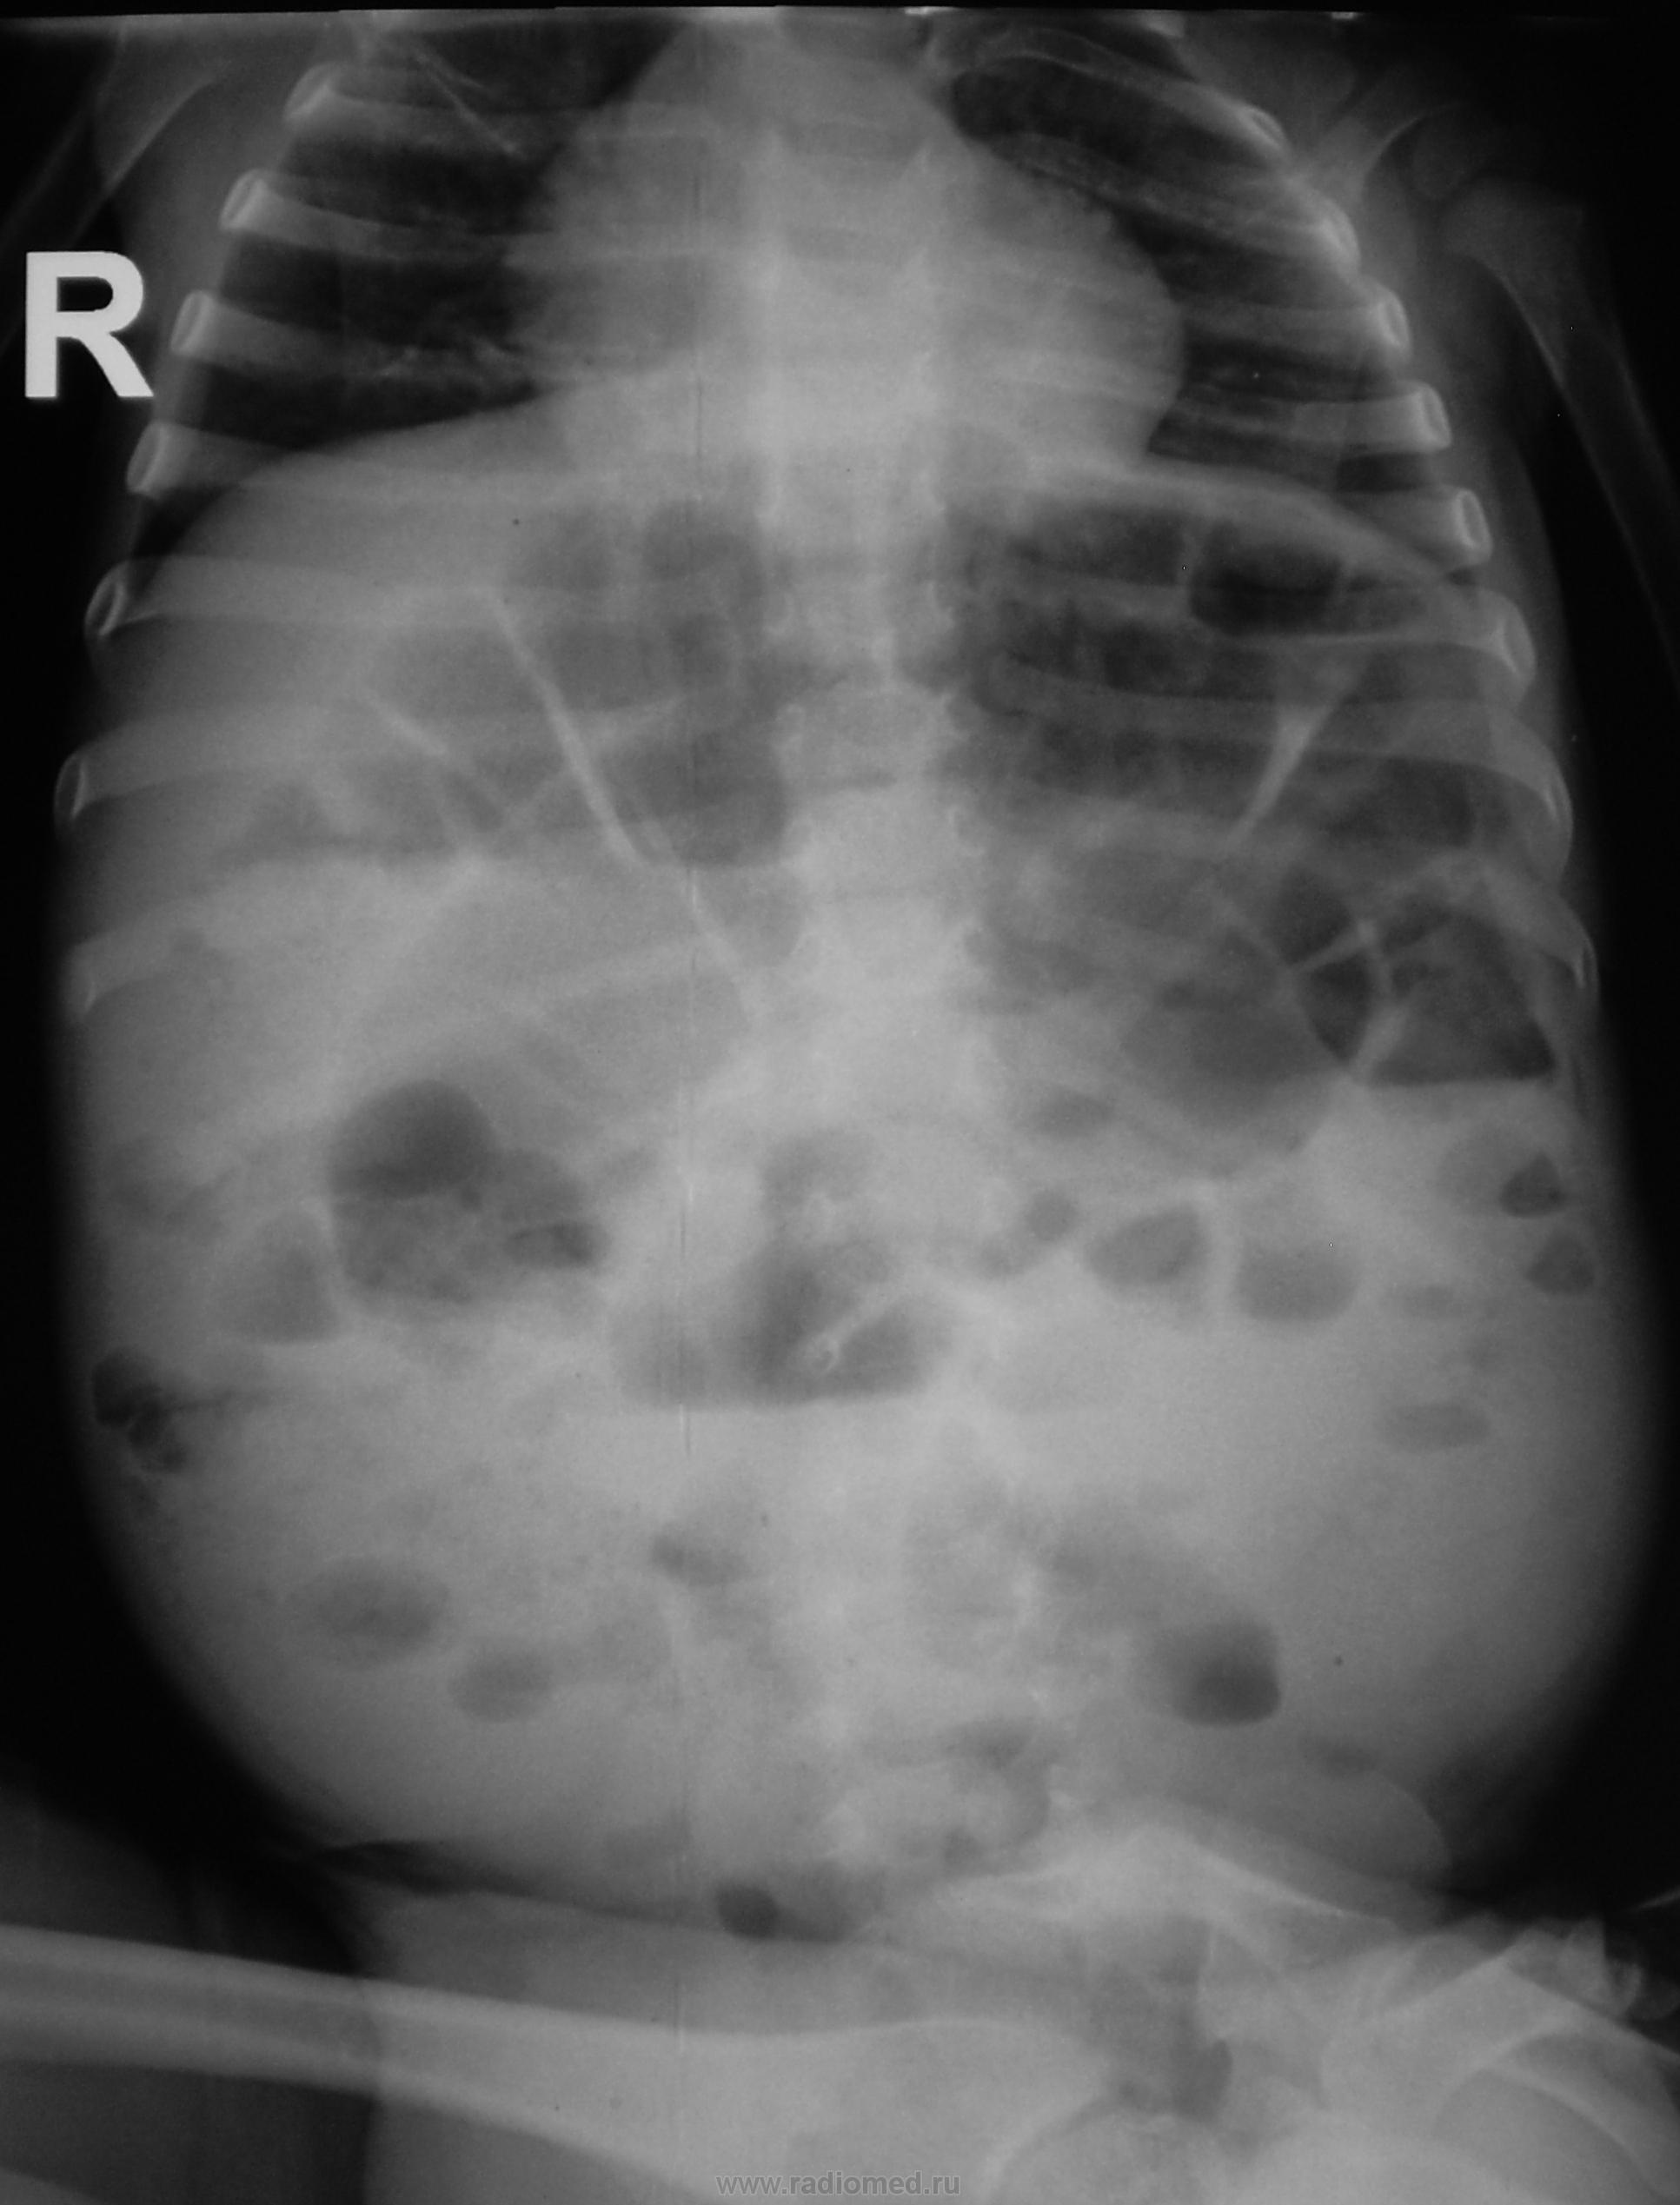

На рентгенограмме толстокишечные "чаши Клойбера". Учитывая клинику, можно думать о болезни Гиршпрунга. Показаны УЗИ, ирригография. Желательно уточнить клинику, возраст.

Мне кажется, что обьем брюшной полости значительно увеличен, также резко увеличены диаметр и длина толстой кишки, очень похоже на мегаколон - вероятнее всего болезнь Гиршпрунга. Могут быть и другие причины, вплоть до банальной диспепсии, но клиника все-таки больше опять за Гиршпрунга. Хорошо бы ирригоскопию сделать, да желательно вместе с хирургом (у нас почти всегда так делается).

Видны резко расширеные петли кишечника с гаутральными перетяжками и горизонтальные уровни жидкости с шириной меньшей высоты газового пузыря.

Жалоб нет. Лечащего врача смущает, что ребенок ест нормально, но нормально не оправляется, оправляется редко, как взрослый - со слов врача.

Навскидку - долихосигма (долихоколон) с дополнительными петлями и изгибами, муковисцидоз, да и неврология...